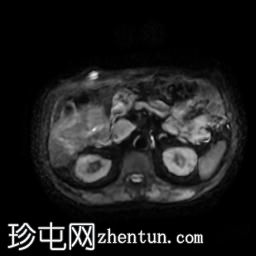

轴位T2加权像

脂肪抑制像

轴位

T2加权像

胆囊切除术后,可见肝总管局部断裂,尤其是在胆囊管开口上方。该断裂伴有胆囊切除部位形成较大的血肿或胆汁瘤。